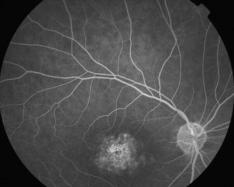

DYSTROPHIE DES CONES